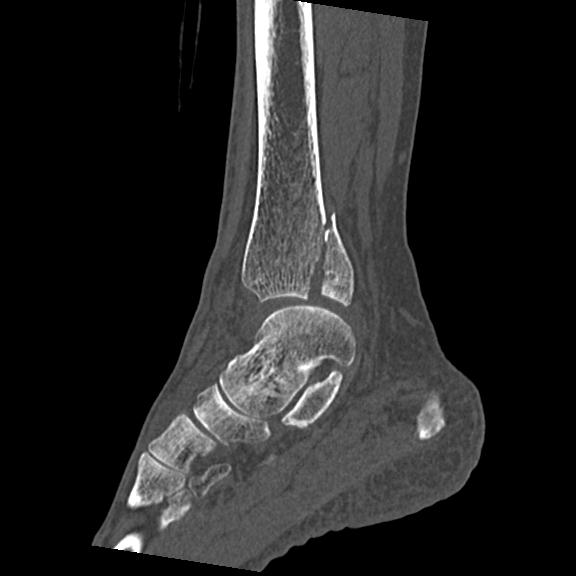

102755 1/4 2R 1/15 2R 右足関節 68歳女性 右三果脱臼骨折